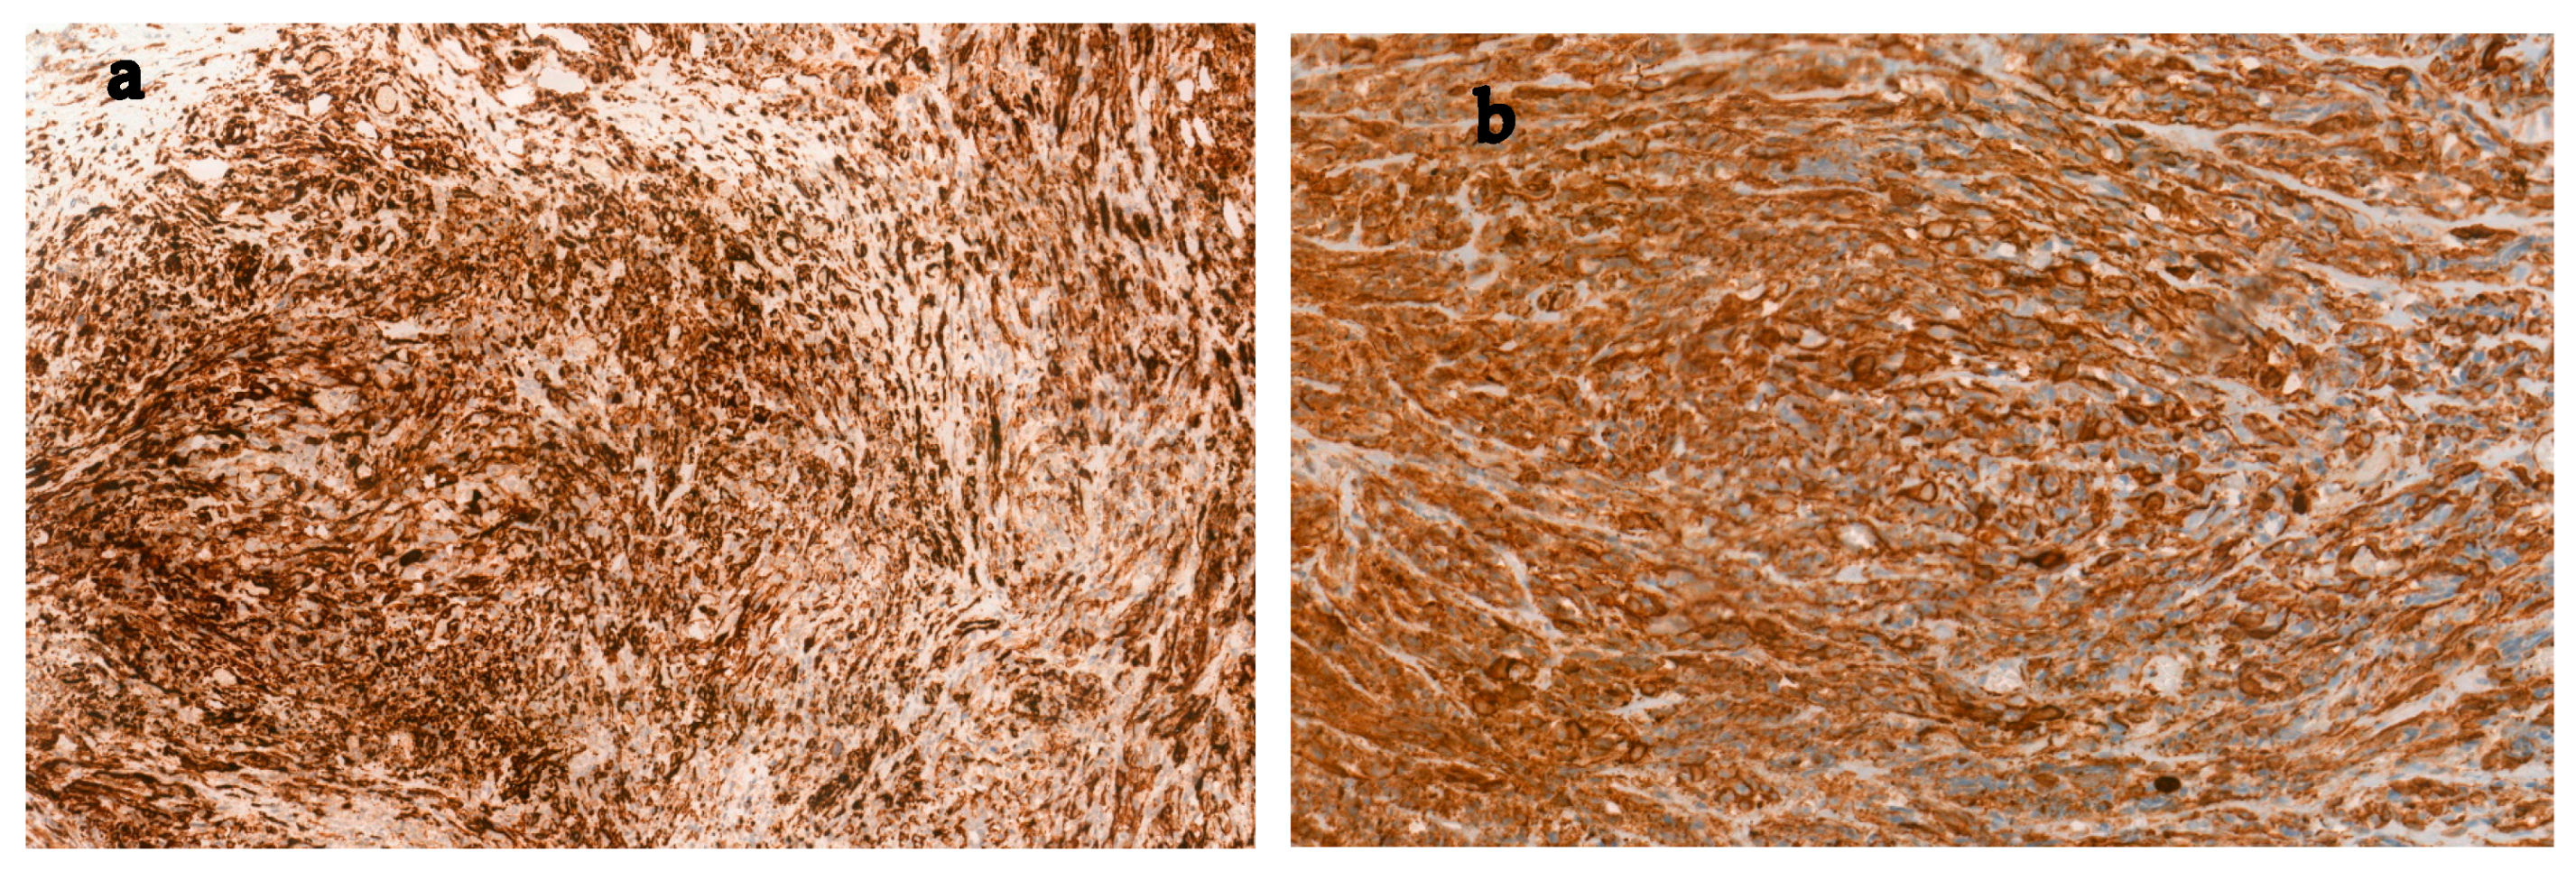

2. Case Report